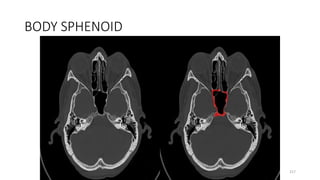

• Ophthalmic artery

SPHENOID BONE BODY

BODY SPHENOID

SPHENOID BODY